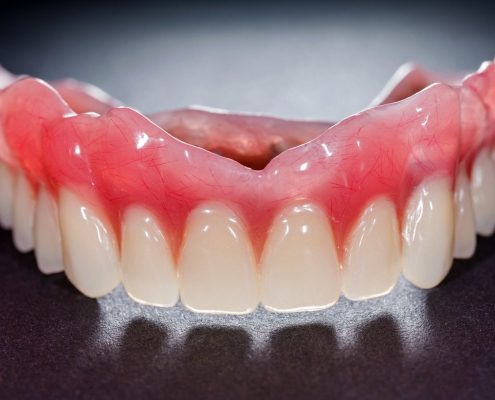

افراد از یک سنی به بعد دندان هایشان شروع به تخریب و ریزش می کنند، از این رو اینگونه افراد مجبور هستند دندان های مصنوعی را جایگزین دندان های طبیعی خود کنند. فناوری CAD CAM  (کدکم) روشی مؤثر و منحصر به فرد در ساختن دندان مصنوعی و روکش های گوناگون و... محسوب می شود. با ما همراه باشید تا در ادامه این مقاله تمام نکات مرتبط با CAD CAM را برای شما بازگو کنیم.